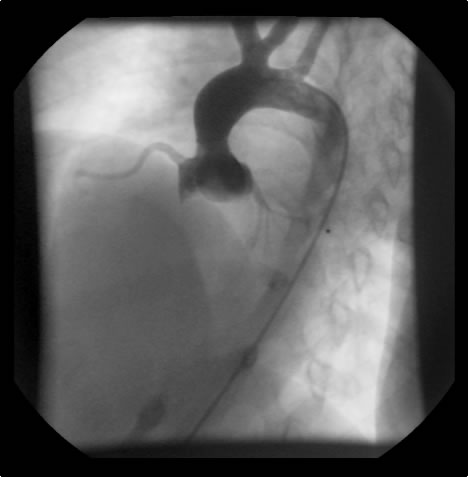

An asymptomatic, 5-year-old, 18-kg boy known by genetic testing to have Williams syndrome on physical examination had a IV/VI harsh systolic ejection murmur and no diastolic murmur.  Preoperative echocardiogram showed an aortic root dimension of 2 cm and the dimension at the level of stenosis in the ascending aorta was 8 mm.  Peak echocardiogram gradient was 70 mm Hg with a cardiac catheterization gradient of 50 mm Hg.  The child had no peripheral pulmonary artery stenosis.

Figure 2: Preoperative cardiac catheterization. Figure 3:The "waist" in the ascending aorta is readily apparent. The "waist" is above coronary orifices. Figure 4: AP/Lateral ventriculogram. The patien has no subaortic obstruction. Figure 5: Main pulmonary artery injection. There is no peripheral pulmonary artery stenosis.